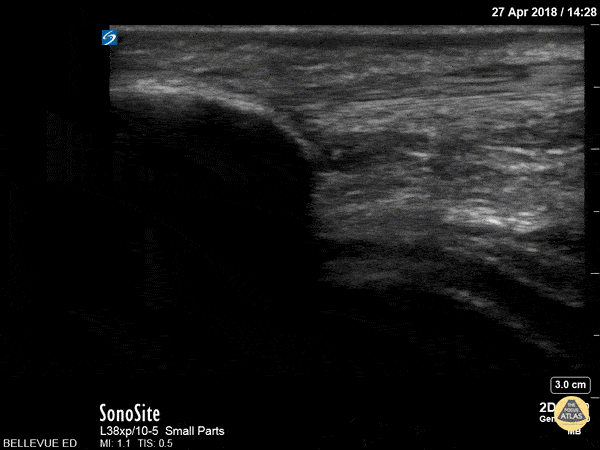

In this clip we see the linear, fibrillar, echogenic patellar tendon in long axis tracking along the top of the screen. It starts with the insertion point at the distal patella (left side of the screen). As the probe moves distally, we see where it attaches to the proximal tibia on the right of the screen. Hannah Kopinksi and Dr. Lindsay Davis - NYU Emergency Medicine